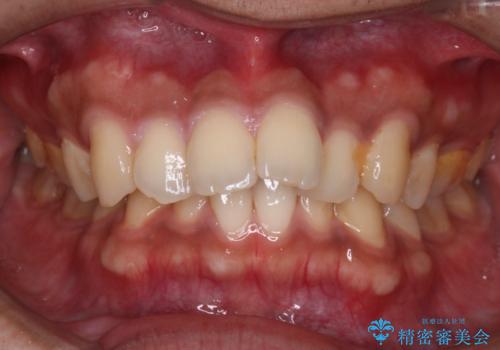

【審美ワイヤー】奥歯のガタガタを治したい

- 歯並びの凸凹を主訴に来院されました。

スペースが必要なため、抜歯を行なって治療を行いました。

奥歯の捻れが強く治療期間がかかりましたが、綺麗な仕上がりに満足していただきました。